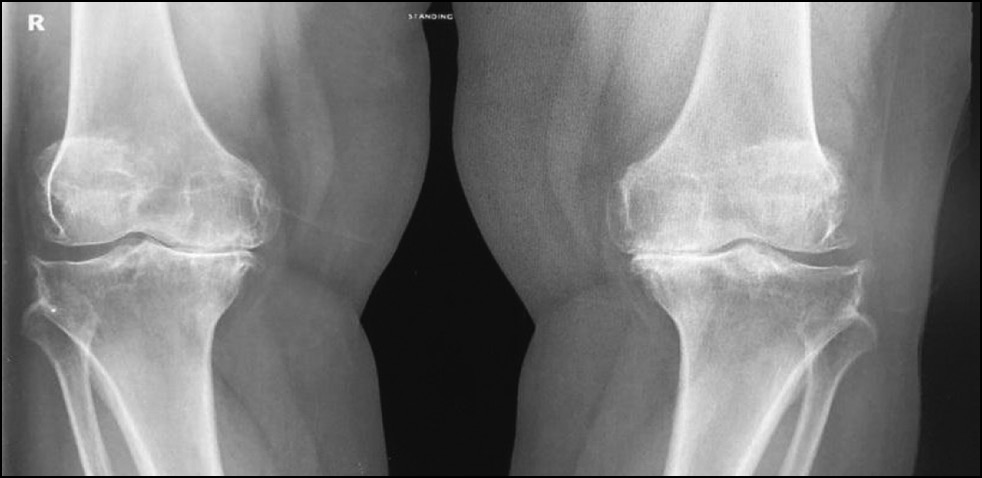

CASE 4. PATIENT 25

Age: 65 years.

Sex: Male.

Diagnosis: Bilateral advanced knee osteoarthritis.

Procedure: Bilateral simultaneous knee arthroplasty.

Associated illnesses: No associated comorbidities.

Postoperative follow-up: No postoperative complications were encountered.

Length of hospital stay: 6 days.

Radiological assessment (Fig. 23–26)

Fig. 23. Ap preoperative x-ray showing bilateral knee osteoarthritis.

Рис. 23. Предоперационная рентгенограмма с двусторонним остеоартритом коленного сустава.